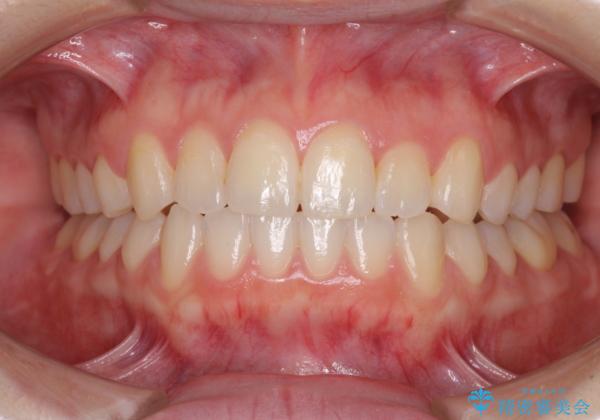

前歯のクロスバイトをインビザライン矯正で改善

- 前歯のデコボコと上下のクロスバイトを気にして来院された患者様です。

インビザラインを用い、IPR(歯と歯の間を削る)と歯列全体を拡大させることで、歯並びを整えていくこととしました。

上の前歯が下の前歯を乗り越える際、奥歯がほとんど咬めない時期があり、乗り越えた後も、インビザライン特有の奥歯の咬みにくさが続きました。

咬み合わせ改善のために治療期間を要しましたが、最終的に奥歯はしっかりと咬めるようになりました。